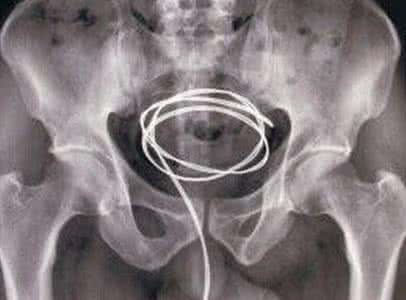

本市一男青年因泌尿系统异物日前到医院就医,医生通过X线检查并询问病情得知,这名男子的膀胱内竟有74颗直径5毫米的磁性小钢珠,而且在磁力的作用下,小钢珠已经黏成一坨了。常规方法,这么大的异物只能切开膀胱才能取出,而该院泌尿外科医生经过详细计划,最终通过微创手术成功取出了全部小钢珠。

由于异物,男子出现尿频、尿急、尿痛和下腹部坠痛、走路时疼痛加重等不适,先后到本市多家医院就诊。医生们发现其膀胱内的异物是由直径0.5厘米的74颗磁钢珠吸附在一起形成了一个团块后,均告知他只能切开膀胱才能取出。患者担心手术创伤太大,不愿接受这样的治疗方式,最后来到医院泌尿外科。

经过缜密分析,该院泌尿外科专家与同事认为,可以通过微创手术取出全部小钢珠。手术中,医生灵活运用膀胱镜等设备,成功将患者膀胱内的“钢珠块”分离成一个个小钢珠,一一取出。目前患者恢复良好,已经出院。

据了解,这些磁性钢珠为益智玩具,在网上很容易买到。由于其磁性极强,小钢珠可以摆成任意造型,也可连成串珠状。对于这么多钢珠是如何进入男子体内的,由于涉及患者隐私,医生并未告知。